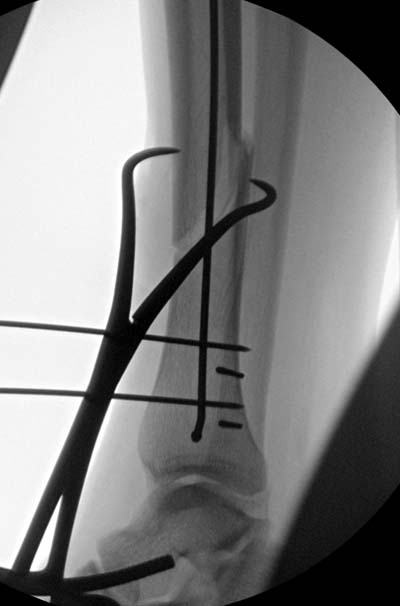

Здесь несколько снимков изолированного перелома большеберцовой с интактной малоберцовой. Weber clamp, блокирующие спицы и риминг в центре канала отрепонировал перелом....